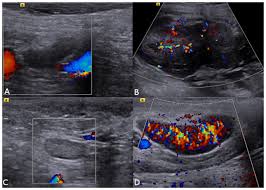

When physicians feel or see enlarged thyroids in a patient's neck, they often will suggest that patients have an ultrasound performed, says risa kent, md, a diagnostic radiologist at yale medicine. Fna might also be used in patients whose cancer has been treated by surgery and/or radiation therapy, to help find out if a neck mass in the treated area is scar tissue or if it's a return (recurrence) of the cancer. But the results are dependent on the experience of the sonographer (radiologist). This test will usually help determine that the nodule has a low chance of being cancerous (has characteristics of a benign nodule), or that it has some characteristics of a cancerous nodule, and therefore a biopsy is indicated. When looking at the lymph nodes in the neck with ultrasound, the following are important criteria which may lead to a fna needle biopsy to confirm disease.

However, an ultrasound can tell if a lymph node has an abnormal architecture possibly because it is infiltrated by tumor. An ultrasound may show your doctor if a lump is filled with fluid or if it's solid. Ultrasound is also used to image the abdominal organs and kidneys, which may be affected by enlarged lymph nodes. If cancer is found in a lymph node, you may need a neck dissection or other additional treatment. The camera remains attached either to a flexible tube called endoscope or to a probe, while it passes within an opening in your body, often your mouth. The primary purpose of the ultrasound is to check for thyroid cancer, and advances in technology have made the test more reliable. There are three ways that cancer spreads in the body. It can be helpful in other areas of the body as well, such as the head and neck area.

Cervical lymph node metastasis plays an essential role in the treatment and prognosis of head and neck cancer patients. The primary purpose of the ultrasound is to check for thyroid cancer, and advances in technology have made the test more reliable. Can help a physician determine what kind of treatment is needed to lower the risk of stroke. Ultrasound an ultrasound is sometimes used, especially to look at the thyroid, salivary glands and lymph glands in the neck. If your cancer diagnosis is based on an ultrasound, it could easily be wrong. The role of ultrasound in the assessment of cervical lymphadenopathy is well established. It can be used with a fine needle aspiration test or core biopsy test to accurately direct the tip of the needle into the lump. This is often called a panorex.

The role of ultrasound in the assessment of cervical lymphadenopathy is well established.